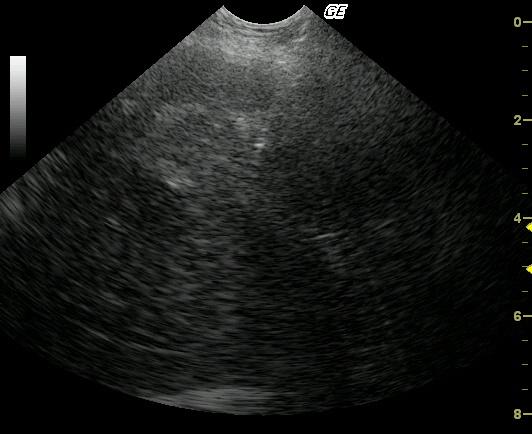

This 14-year-old MN Springer Spaniel was presented for decreased appetite, vomiting, and melena that was non responsive to medical therapy. The clinical condition was rapidly declining. The physical exam was uneventful. Blood analysis revealed a progressively, mildly elevated ALT and mildly elevated SAP in serial samples over a 3-week period